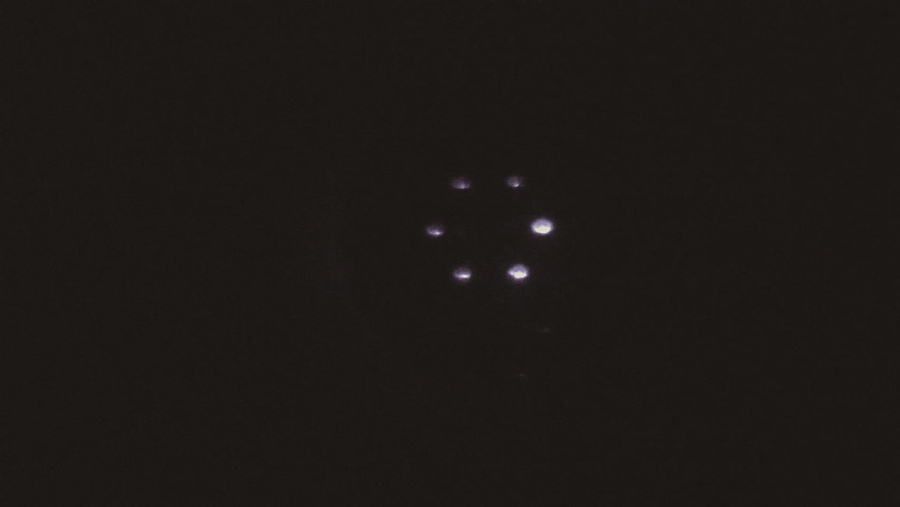

Five volunteers were recruited inside the laboratory, and the operator measured the subject’s left eye using the system experimental prototype and randomly showed the result of the eye axis length, radius of curvature, anterior chamber depth, and images of the measured human eye on the wavefront aberration sensor (Fig.3, Fig.4, Fig.5, Fig.6). The quality of the acquired images was good. The experimental prototype was used to measure the standard eye model with different diopters. The results of the single-sample t-test showed that the significance of the P value was greater than 0.05 (Table 1), and there was no difference between the diopter detection value of the experimental prototype and the standard value of the standard eye model, indicating that the experimental prototype could ensure measurement accuracy. From the values of Sw and TRT, it can be deduced that both the ocular biological parameters and diopter measurements have high repeatability. The CoV of eye biological parameters was less than 3%, the variation in the axial length and corneal curvature was smaller (CoV is less than 0.256%), and the ICC was higher than 0.6, reflecting high consistency (Table 2). The Bland-Altman analysis of the eye axis length, radius of curvature, and anterior chamber depth measured by the experimental prototype and IOL Master 500 showed no significant difference (P>0.05); the difference range was very small, and the 95% consistency limit was -0.045-0.056 mm, -0.037-0.056 mm, -0.534-0.355 mm, respectively, and all the measurement results were within the consistency interval (Table 3).

2.3 角膜曲率测量光路设计

角膜曲率测量光路的设计原理是角膜反射成像。角膜曲率测量方法为:6个呈正六边形排布的LED光源(S21、S22等)经过1 mm孔径光阑(I21、I22等)后变为点光源,点光源经透镜(L21、L22等)准直后投射到角膜前表面,角膜反射的图像经L7、L8及L10~L13组成的物方远心光路后成像在CCD2上;利用重心算法求出角膜反射图像中位于正六边形长对角线上的两个点光源的距离,便可求得角膜曲率。

在实验室内招募了5名志愿者,因为都是年轻人群,因此没有设置排除条件。虽然这5名志愿者的眼球有不同的屈光状态,但基本都是健康的。采用本团队搭建的实验样机对5位受试者的左眼进行测量,采集的典型结果如